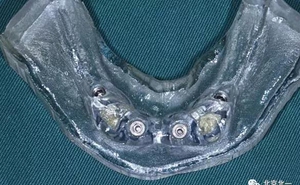

圖三:終末導(dǎo)板

圖四:導(dǎo)板工具

圖十六:術(shù)后三個(gè)月永久修復(fù)取模,夾板固定。

圖十七:拍X片確認(rèn)無誤差